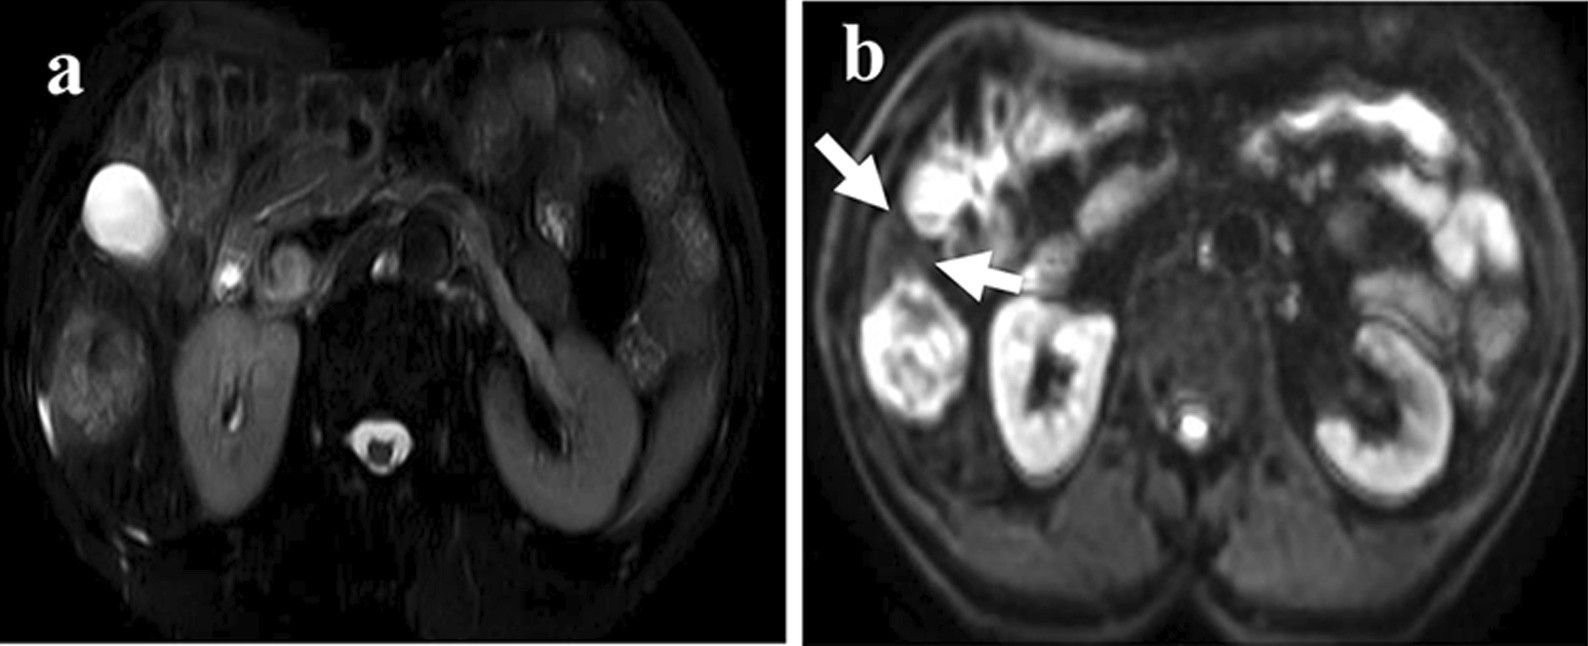

Fig. 3From: Value of gadoxetic acid-enhanced MRI for microvascular invasion of small hepatocellular carcinoma: a retrospective studyA 69-year-old woman with sHCC with MVI. a T2WI shows a high signal intensity hepatic mass with round shape and smooth margins. b DWI shows mismatch region compared to T2WI (thin arrow)Back to article page